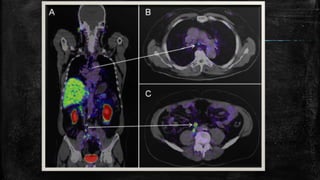

Oncology

▪ Tracers used commonly include fluorine-18 (18F) fluoro-

deoxyglucose (FDG), called FDG PET.

▪ FDG being a glucose analog, gets picked up by the cells.

▪ Glucose gets phosphorylated by hexokinases. The values of the

mitochondrial form of this enzyme are raised in cancers that are

rapidly growing. In locations of cancer, the metabolic activity is

quite high; hence the glucose uptake is quite high. So this 18F-FDG

also gets taken up quite significantly in these locations, and then this

shows up as a bright spot on the PET scan. This helps in the

detection of metastasis also.